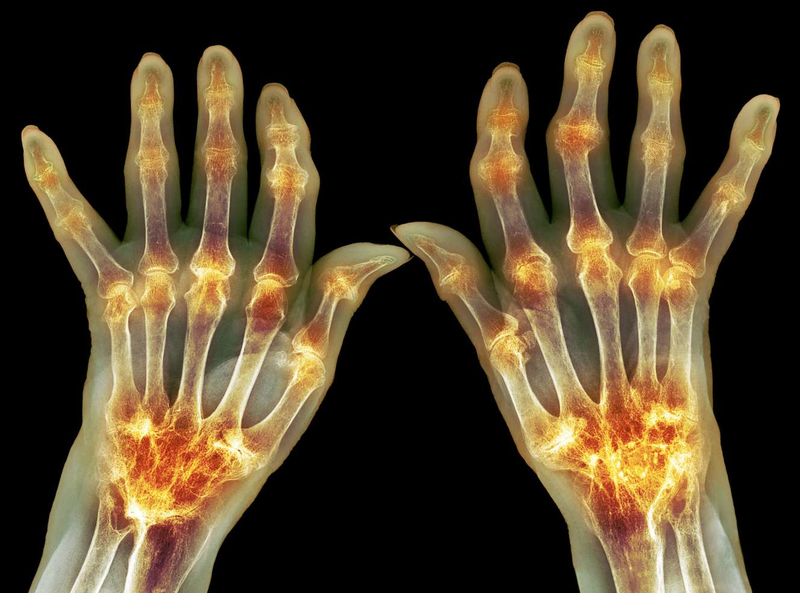

Căn bệnh viêm khớp dạng thấp là tình trạng viêm khớp hệ thống và toàn thân, gây ra do rối loạn hệ miễn dịch, tiến triển mãn tính và nặng dần, sẽ gây ra đau đớn và thậm chí có thể tàn phế. Tỷ lệ mắc bệnh thường cao hơn ở nữ (khoảng 75%), tuổi từ 30 - 60.

Viêm khớp dạng thấp lâu ngày sẽ có thể dẫn tới dính khớp, teo cơ, biến dạng khớp, thậm chí có thể dẫn đến tàn phế. Có khoảng 89% người bệnh gặp phải tình trạng bàn tay khó cầm nắm, cứng khớp, khó đi lại, sau 10 năm đã khởi phát bệnh.